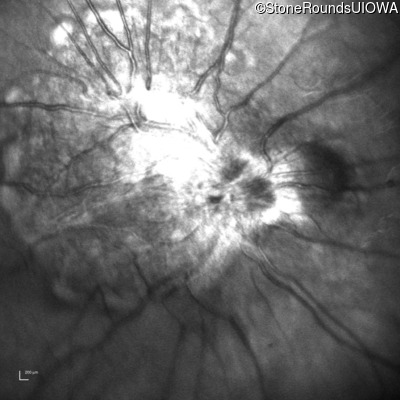

This 9 year old male was noted to have some crossing of his eyes at 2 months of age and the eye exam which followed identified a retinal lesion in the right eye. When he was six years old an epiretinal membrane was noted in his left eye. Two years later it was decided that it was a thin hamartoma in that eye as well. He underwent neuroimaging at age 7 which identified bilateral acoustic neuromas.

| Age at visit: 7 years |

| Age at visit: 8 years |